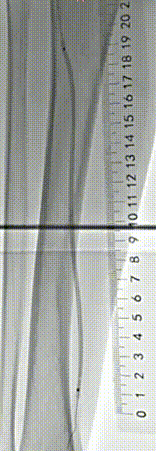

▲术前血管造影与CTA相符

▲采用导丝通过支架内闭塞段顺利,考虑为内膜增生合并部分陈旧性血栓病变,再次造影明确病变长度。